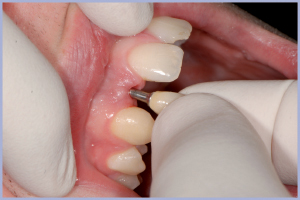

- Fig. 17 – Inserimento permanente del moncone in titanio

- Fig. 27 – Inserimento permanente del moncone in titanio